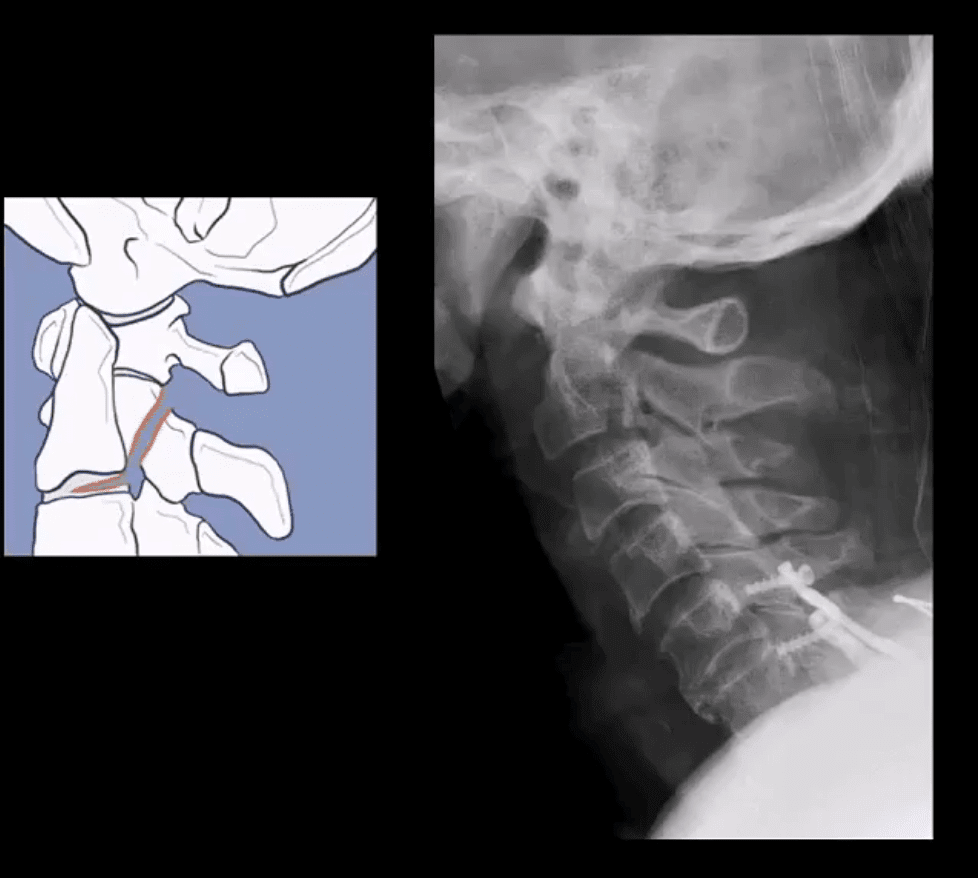

- Hangman’s Fx aka traumatic spondylolisthesis of C2 with a fracture of pars interarticularis or pedicles (unstable)

- Associated injuries: 30% have other c-spine fx especially Extension teardrop at C2 or C3 due to avulsion by ALL

- Hangman fx and extension teardrop

- Imaging: initial x-radiography then CT that helps to delineate another injury such as facet/pedicle Fx further. MRI may help if complicated by Vertebral A. damage

- Management: if type 1 injury then closed reduction and rigid collar for 4-6 weeks, halo bracing if type 2 (>3-5mm displacement) Fx/instability, anterior or posterior spinal fusion at C2-3 if type 3 Fx (>5-mm displacement)